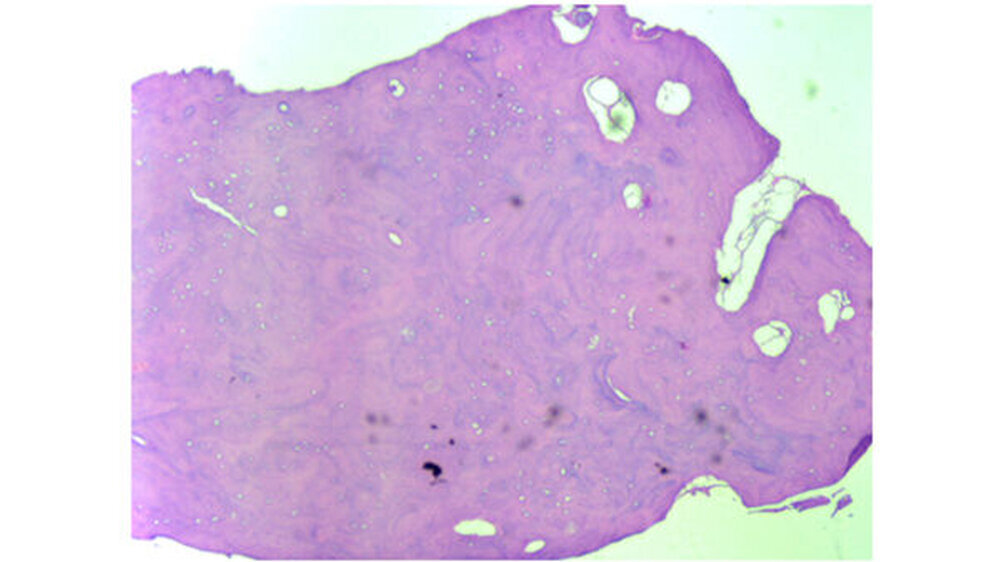

Klinisch zeigte sich, dass die knöcherne Veränderung nicht mit Blutgefäßen durchsetzt war. Erst nach vollständiger Entfernung konnte in der Defekttiefe aus der angrenzenden lingualen Spongiosa eine Blutung provoziert werden. Histologisch wurde ein Osteom aus kompaktem, regressiv verändertem Lamellenknochen mit überwiegend leeren Osteozytenlakunen sowie sehr vereinzelt unreifes Osteoid mit aktivierter Bindegewebszone nachgewiesen.